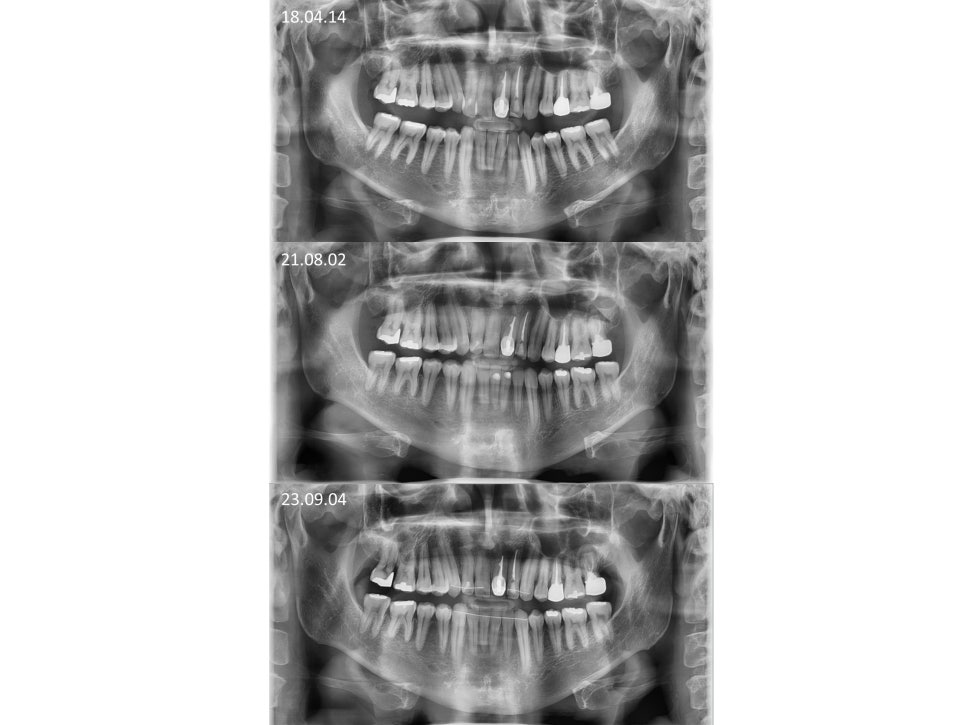

ºñ¼ö¼ú ÁÖ°ÆÅÎ ±³Á¤Ä¡·á ÀüÈÄÀÇ

¿·¾ó±¼ ¿¢½º·¹ÀÌ ÀÔ´Ï´Ù.

ºñ¼ö¼ú ÁÖ°ÆÅÎ ÀüÈÄ ±³ÇÕÀÔ´Ï´Ù.

¾Æ·¡ÅÎÀÌ ¸¹ÀÌ ¾ÕÀ¸·Î ³ª¿ÍÀÖ¾ú´Âµ¥

¾ç¾Ç¼ö¼úÀÌ ¾Æ´Ï¶ó

±³Á¤Ä¡·á ¸¸À¸·Î

±³ÇÕÀÌ Àß °³¼±µÈ °ÍÀ»

º¼ ¼ö ÀÖ½À´Ï´Ù.

ºñ¼ö¼ú ÁÖ°ÆÅÎ ±³Á¤Ä¡·á ÀüÈÄÀÔ´Ï´Ù.

Á¤»ó±³ÇÕÀ¸·Î

°³¼±ÀÌ Àß µÇ¾ú°í

ºñ¼ö¼ú ÁÖ°ÆÅÎ ±³Á¤Ä¡·á ÈÄ

2³âÀÌ °æ°ú µÇ¾îµµ

ÁÁÀº ±³ÇÕÀ» Àß À¯ÁöÇϰí À־

³Ê¹« ´ÙÇàÀÌ¿´½À´Ï´Ù.

ºñ¼ö¼ú ÁÖ°ÆÅÎ ±³Á¤Ä¡·á·Î

°³¼±ÀÌ µÇ¾ú°í

½Ã°£ÀÌ Áö³ªµµ

ÁÁÀº ±³ÇÕÀÌ Àß À¯ÁöµÇ°í ÀÖ½À´Ï´Ù.

Ä¡¾Æ °Ç°­»óŵµ

¾çÈ£ÇϰÔ

Àß À¯ÁöÇÏ°í °è½Ê´Ï´Ù.